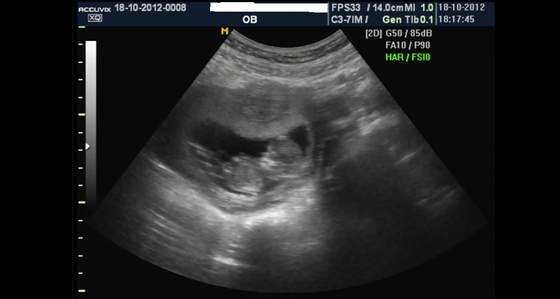

Dołączam zdjęcie mojego 4,5 cm szczęścia.